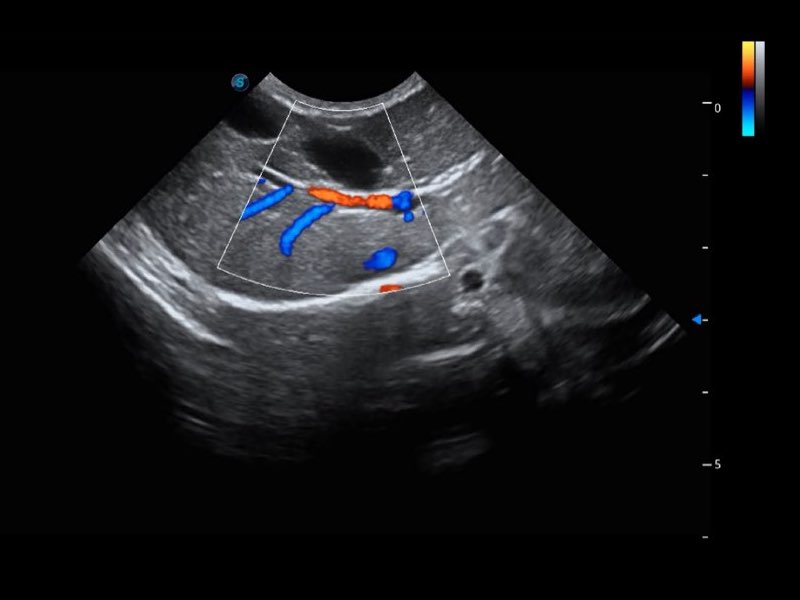

Przy pracach nad aparatem ProPet 60 uwzględniono najważniejsze preferencje i potrzeby weterynarzy, oferując finalnie przystępne cenowo i odpowiednio wyważone połączenie znakomitej precyzji klinicznej, zwiększonej wydajności i przemyślanego przebiegu pracy, niezastąpione w codziennej praktyce weterynaryjnej. Dzięki dostępowi do pełnej gamy głowic HD rozwiązanie to spełnia wszystkie potrzeby w zakresie obrazowania, umożliwiając wykonywanie badań jamy brzusznej, małych narządów, ortopedycznych, badań podczas rozrodu, a nawet badań serca i klatki piersiowej, a to wszystko przy doskonałym stosunku jakości do ceny.